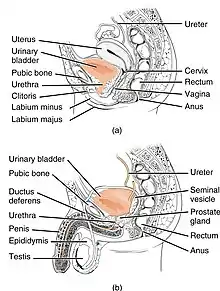

The urethra transports urine from the bladder to the outside of the body. This image shows (a) a female urethra and (b) a male urethra. | |

The urethra (from Greek οὐρήθρα – ourḗthrā; pl.: urethras or urethrae) is a tube that connects the urinary bladder to the urinary meatus for the removal of urine from the body of both females and males. In human females and other primates, the urethra connects to the urinary meatus above the vagina, whereas in marsupials, the female's urethra empties into the urogenital sinus.[1]

Females use their urethra only for urinating, but males use their urethra for both urination and ejaculation.[2] The external urethral sphincter is a striated muscle that allows voluntary control over urination.[3] The internal sphincter, formed by the involuntary smooth muscles lining the bladder neck and urethra, receives its nerve supply by the sympathetic division of the autonomic nervous system.[4] The internal sphincter is present both in males and females.[5][6][7]

The urethra is a fibrous and muscular tube which connects the urinary bladder to the external urethral meatus. Its length differs between the sexes, because it passes through the penis in males.

Female

In the human female, the urethra is about 4 cm long,[8] and exits the body between the clitoris and the vagina, extending from the internal to the external urethral orifice. The meatus is located below the clitoris. It is placed behind the symphysis pubis, embedded in the anterior wall of the vagina, and its direction is obliquely downward and forward; it is slightly curved with the concavity directed forward. The proximal two-thirds of the urethra is lined by transitional epithelial cells, while the distal third is lined by stratified squamous epithelial cells.[12]

Between the superior and inferior fascia of the urogenital diaphragm, the female urethra is surrounded by the urethral sphincter.